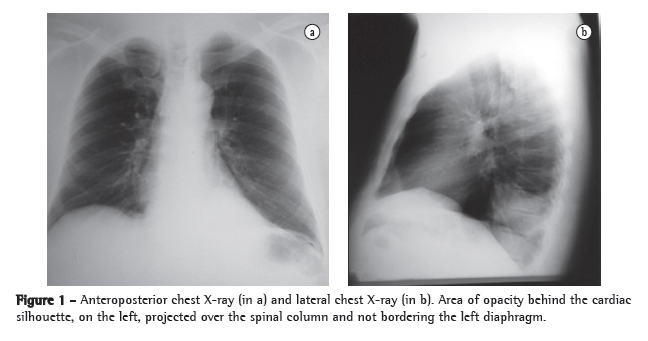

Physical examination revealed good general health, no fever, an HR of 88 bpm and an arterial pressure of 90-145 mmHg. The cardiac auscultation was normal, and examination of the lung revealed reduced expansion and diminished breath sounds in the lower third of the left hemithorax, as well as dullness to percussion in this same region. The rest of the physical examination revealed no abnormalities. The results of the laboratory tests performed at admission, such as blood workup, lipid profile, coagulation profile, determination of electrolyte concentrations, renal function test and hepatic function test, were normal. The ESR was 32 mm/h. Serology for HIV was negative. A chest X-ray at admission revealed opacity in the posterior segment of the left lower lobe (Figure 1). A CT scan of the chest with two-dimensional reconstruction revealed an aortic branch directed toward the pulmonary opacity (Figure 2), which is consistent with a diagnosis of pulmonary sequestration. The patient was referred for surgery, and a left lower lobectomy was performed to resect the anomalous pulmonary tissue (Figure 3). After the macroscopic analysis of the surgical sample, the patient was diagnosed with intralobar sequestration. The postoperative evolution was favorable, and the patient was discharged to outpatient treatment.

In the investigation of a suspected case of pulmonary sequestration, imaging studies have two principal objectives: to rule out other pathologies; and to confirm the presence of an anomalous arterial supply.(12-15) The most common radiological presentation is a ­homogeneous opacity in the posterior basal segment of the left lower lobe. Arteriography allows the characterization of anomalous arteries, providing valuable information for preoperative planning.(13) Similarly to nuclear magnetic ­resonance imaging, spiral CT allows the visualization of the source and course of the vessels in most cases. In such cases, angiography is unnecessary.(10,15) The diagnosis of pulmonary sequestration is confirmed by multichannel CT scans of the chest with intravenous contrast and reconstruction, there being no need for aortography or magnetic resonance imaging of the chest and abdomen, since CT scans of the chest and upper abdomen allows the visualization of the arterial vessel communicating with the sequestration and of the changes in the lung parenchyma.(14,15)

In this report, the patient reported two previous episodes of massive hemoptysis one week earlier and had an area of opacity behind the cardiac silhouette in the left base. The patient had no weight loss, and his overall health status was preserved-data that argued against a neoplastic etiology. The patient reported no history of comorbidities or recurrent infections. He was admitted for diagnostic investigation. Chest CT scans with intravenous contrast and two-dimensional reconstruction revealed pulmonary sequestration with individualization of the anomalous arterial supply. The patient underwent surgery, in which the anomalous pulmonary tissue was resected, and, after the macroscopic analysis of the sample, was diagnosed with intralobar sequestration. The case presented here is rare. The postoperative evolution was favorable, and the patient was discharged to outpatient treatment.